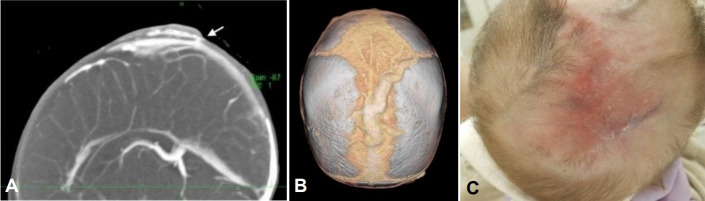

Aplasia cutis congenita with unique vascular malformation and cranial hypoplasia: a case in a preterm infant.